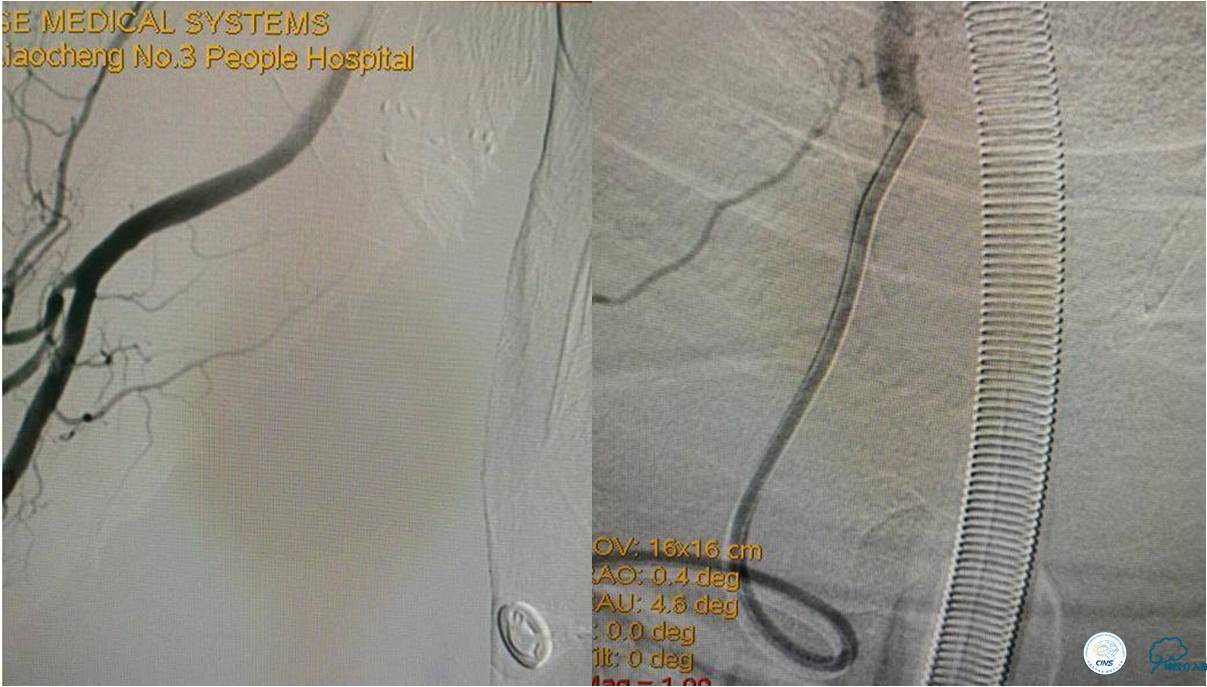

》DSA资料(右侧椎动脉)

★后循环取栓病人,若股动脉入路较差,可以考虑经桡动脉进行。

★基底动脉尖端的血栓偏向哪侧,应该将Solitaire支架放入同侧的大脑后动脉,这样取栓的成功率较高一些。